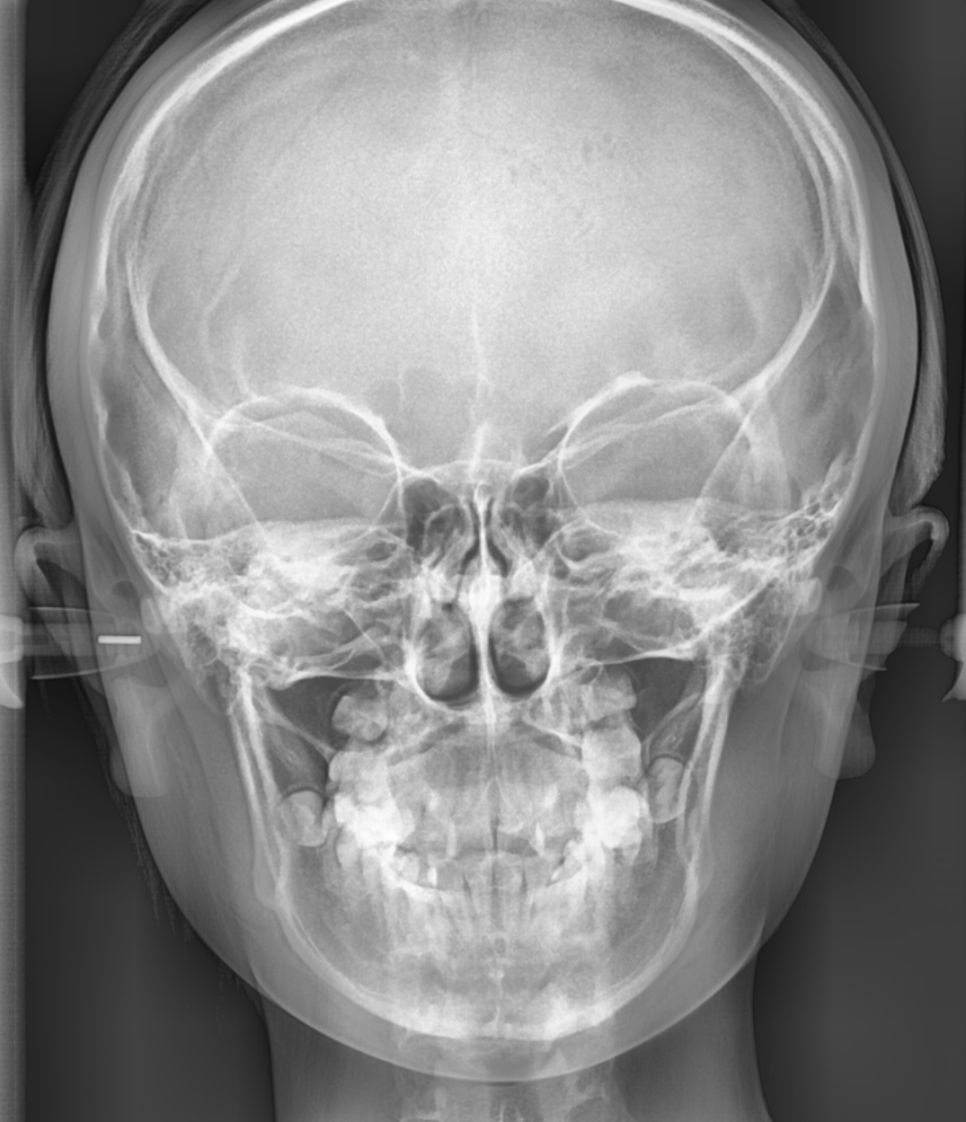

정밀한 엑스레이

얼굴 라인 분석등을 통해 진단됩니다.

턱관절에도 문제가 없는지 판단해야하고요

골격 구조, 치아 배열, 입술의 돌출 정도 등

개인별 분석을 통해 알 수 있으니